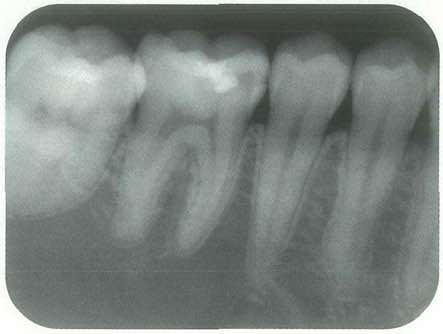

28歳の男性。下顎右側第一大臼歯の疼痛を主訴として来院した。3年前に治療を受けたが,数日前から30分ほどの自発痛が間欠的に起こるという。電気診で閾値が低下している。初診時の口腔内写真とエックス線写真とを別に示す。

スクリーンショット 2017 01 19 16 04 58スクリーンショット 2017 01 19 16 05 03

A グラスアイオノマーセメントで裏層し,コンポジットレジン修復

B 水酸化カルシウムで間接覆髄し,コンポジットレジン修復

C 酸化亜鉛ユージノールセメントで間接覆髄し,コンポジットレジン修復

D 水酸化カルシウムで直接覆髄し,コンポジットレジン修復

E 酸化亜鉛ユージノールセメントで仮封し,経過観察

正答 E

問題文に「間欠的な自発痛」とあるので、CR修復など最終修復に進んではいけません。もし「自発痛」が「冷水痛」であればそれが正答になりえますが、今回の場合は、歯髄の炎症が大きいので、「歯髄鎮静療法」を選ぶ必要があります。鎮静療法につかえるお薬は、ユージノールとフェノール系の2種でしたね。ユージノールは歯髄炎が広まりかけている組織を殴って!黙らせるようなお薬です(アグレッシブ!)。それで歯髄炎が収まれば、歯髄保存しCR充填できますし、自発痛が止まらなければ全部性の歯髄炎に移行したと判断され、抜髄となります。

今回はとりあえず、ユージノールということでCかEが残ろいますが、Cのユージノール+CRは「重合阻害」を起こすのでアウトです!よって、正答はEとなりなす。

104B-4

35歳の男性。下顎右側第一大臼歯の違和感を主訴として来院した。2週前にう蝕の治療を受け,その数日後から自覚しているという。右下6はレジン系仮封材で充填されており,間欠的な咬合痛と冷水痛とがある。歯髄電気診に反応する。仮封材除去前のエックス線写真と仮封材除去前後の口腔内写真とを別に示す。適切な処置はどれか。1つ選べ

スクリーンショット 2017 01 19 16 07 27

スクリーンショット 2017 01 19 16 07 34a IPC法

b 抜髄法

c 直接覆髄法

d メタルインレー修復

e 光硬化型グラスアイオノマーセメント修復

正答 d

こちらは、歯髄が正常と判断できます。「自発痛」ではなく「間欠的な冷水痛」で、歯髄電気診で反応しているからです。よって、最終的な修復=メタルインレー修復にうつることができます。もちろん、歯髄に近接していて刺激が伝わってしまいそうなときには、間接覆髄や裏層などお薬をつめることを途中ではさむかもしれませんが、大枠の治療方針としてはメタルインレー修復が妥当となります。問題文の冷水痛が、自発痛だったりすると、「歯髄鎮静療法」や「抜髄」を考えていかなければならなくなります。